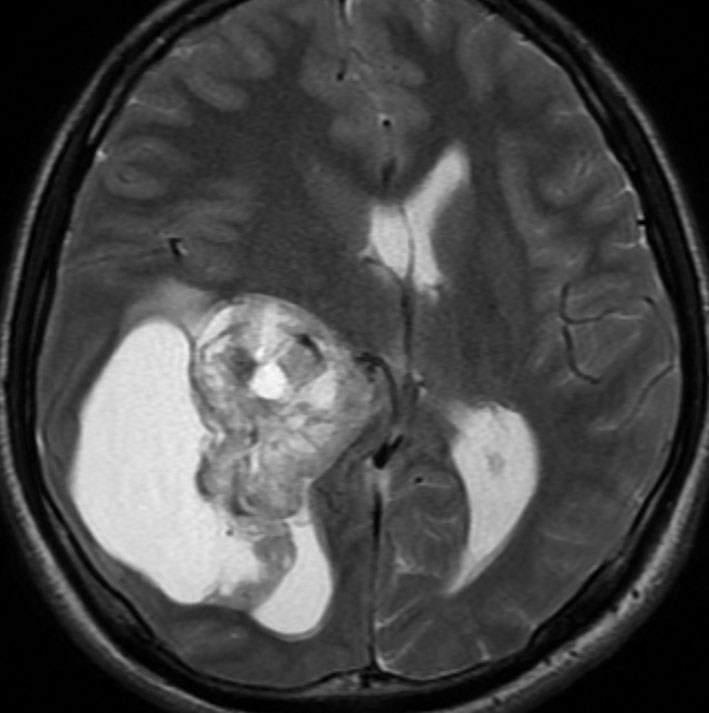

第4脳室床に発生した典型的な上衣腫 EPN-PFA の画像です。水頭症になって,頭痛と嘔吐,意識障害で発症しました。典型的なMRI画像と病理所見です。MRIでは第4脳室からマジャンディー孔を越えて脊髄背側まで長く腫瘍が伸びています。腫瘍内部に小さなのう胞が複数みられます。病理像では,血管周囲に細胞核がない無核野が認められます。血管周囲に伸びた繊細な単極性突起が集まった領域です。これは,血管周囲偽ロゼット perivascular pseudorosette という上衣腫に特徴的な病理所見です。

幼児の巨大な上衣腫です。左ルシュカ孔から延髄を取り囲む様に小脳延髄角槽に進展しています。最も典型的で治療が難しいタイプです。これはT2強調画像ですが,ガドリニウム増強されないものでした。

左が術前,右が術後です。脳底動脈の周囲が摘出できませんでした。幼児ですが手術後には局所照射をするしか方法がありません。